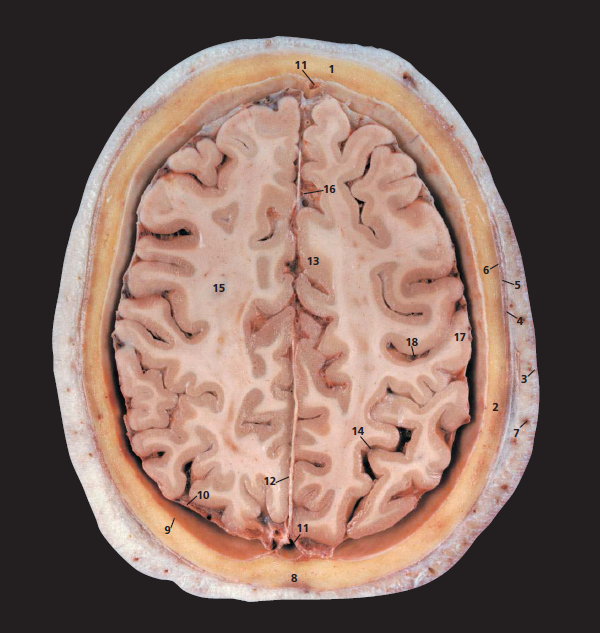

5 Temporalis 6 Pericranium

7 Branch of superficial temporal artery

8 Sagittal suture 9 Dura mater

10 Arachnoid mater 11 Superior sagittal sinus

12 Falx cerebri 13 Cingulate gyrus

14 Parieto-occipital sulcus

15 Corona radiata

16 Anterior cerebral artery (branches)

17 Postcentral gyrus 18 Central sulcus